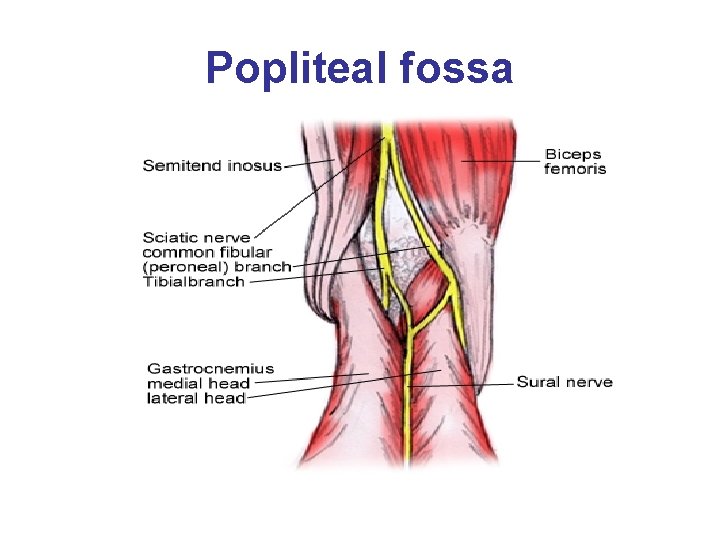

Popliteal Sciatic Block • Anesthetizes the entire leg below the tibial plateau except the skin of the medial aspect of the calf and foot (saphenous nerve distribution) • The popliteal block is performed on the sciatic nerve proximal to this bifurcation; about 10 cm from the popliteal crease. • Landmarks include the popliteal crease, tendons of the biceps femoris and the semitendonisimus muscles • Used for minor surgeries of the distal lower leg, foot or ankle

Popliteal fossa

Popliteal Sciatic Block • Pt. is positioned in the prone position or in a modified exaggerated lateral position with the leg to be blocked uppermost and flexed at the knee touching the bed and the underlying leg straight. • Advantages are improved calf tourniquet tolerance and an immobile foot. • Complications may be persistent foot drop with potential pressure necrosis